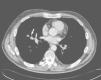

Case reportA 56-year-old man with a previous history of adenoid cystic carcinoma of the right maxillary sinus (pT4N0Mx) that had been treated by right radical hemimaxillectomy and radiotherapy 11 years earlier was admitted to our institution after referral from his oncologist. During the regular follow-up, a computed tomography (CT) scan showed a 2.5cm diameter nodule, with irregular morphology in the middle lobe, which was in contact with the middle lobe brochus and right inferior lobar artery (Fig. 1). A transbronchial biopsy with bronchoscopy was performed showing an epithelial neoplastic cell proliferation with large cytoplasms and hyperchromatic nuclei. Neoplastic cells expressed Cytokeratin AE1/AE3, Cytokeratin 7 and TTF-1. With these features, non-small cell carcinoma with immunohistochemical stigmas of adenocarcinoma was diagnosed. A positron emission tomography (PET) demonstrated a focus of increased FDG uptake in the right hilum contacting with the middle lobe.